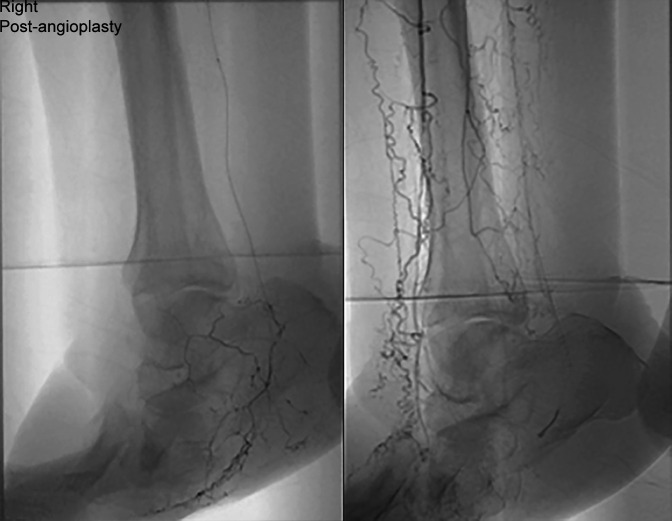

Charcot神经关节病累及足部是糖尿病的一种常见且潜在的破坏性并发症。除了良好的糖尿病控制,外科鞋和定期足部治疗,纠正足部畸形,防止溃疡,深部感染和肢体丧失,现在已经很好地建立了。血管功能不全在这组患者中很常见,传统的血管重建术并不总能成功治愈溃疡和治疗重症缺血。它会影响伤口和骨头的愈合。我们报告了在传统血运方法未能纠正严重缺血的情况下,成功使用改良的胫骨皮质横向运输技术(TTT)。我们已经用这种技术成功地治愈了软组织和骨骼。如何引用本文:Al Omar H, Lahoti O, Edmonds M,等。缺血Charcot中足重建联合胫骨外侧皮质横向转运1例。创伤肢体重建2025;20(1):50-55。

Charcot neuroarthropathy involving foot is a frequent and potentially a devastating complication of diabetes. In addition to good control of diabetes, surgical shoes and regular podiatric treatment, correction of foot deformity to prevent ulceration, deep infection and limb loss are now well established. Vascular insufficiency is common in this group of patients and traditional revascularisation procedures do not always succeed in healing ulcers and treating critical ischaemia. It compromises wound and bone healing. We report successful use of a modified technique of tibial cortex transverse transport (TTT) in a case where traditional revascularisation methods failed to correct critical ischaemia. We have achieved successful soft tissue and bone healing using this technique.